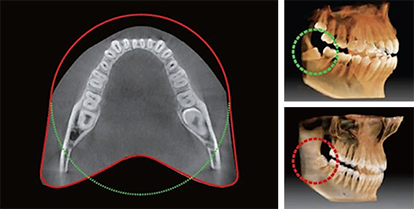

FOV anatomico 12×9

L’innovativo FOV di Smart Plus offre un volume con forma ad arcata, che consente una visualizzazione più ampia della dentizione rispetto ad altri dispositivi con lo stesso FOV. Il volume ad arcata permette di visualizzare anche le aree dentali normalmente nascoste.